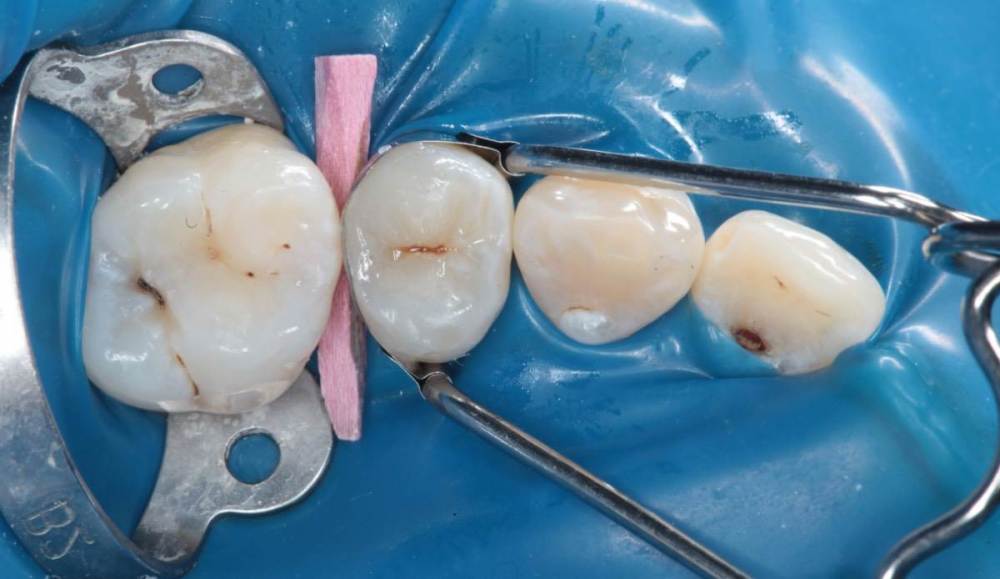

Гарриевич Опубликовано 21 мая, 2022 Поделиться Опубликовано 21 мая, 2022 (изменено) Будущее за регенеративной эндодонтией?) лечение в 2 посещения из-за нехватки времени (новый ассистент, перегруз пациентами, мысли о поднятии стоимости лечения, гипердиагностика?) глубокая пульпотомия, триоксидент, композит. фото подробно выложил это снимок с временной пломбой мало ли что вы подумаете Изменено 21 мая, 2022 пользователем Гарриевич 1 Ссылка на комментарий